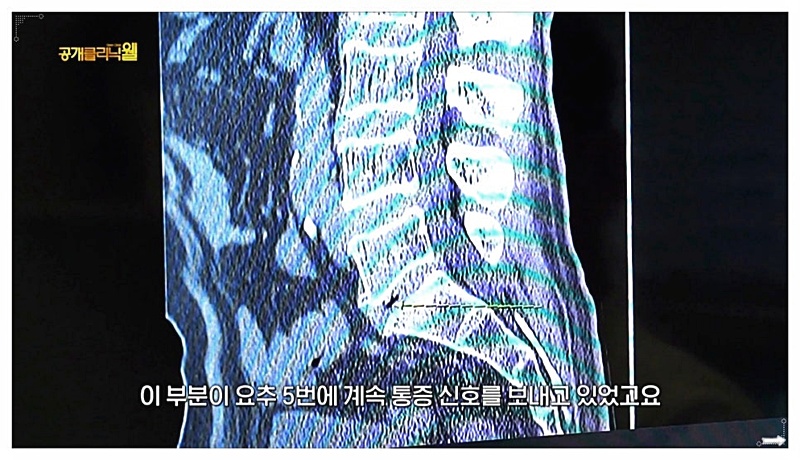

특히 요추 3, 4, 5번 부위에 통증이 집중된다면, 단순히 그 부위가 약해서라기보다

몸 전체 균형이 무너져 체중과 압력이 특정 지점으로 쏠리고 있을 가능성도 있습니다.

요추 3, 4, 5번 부근이 묵직하고 다리로 저릿한 감각이 이어진다거나,